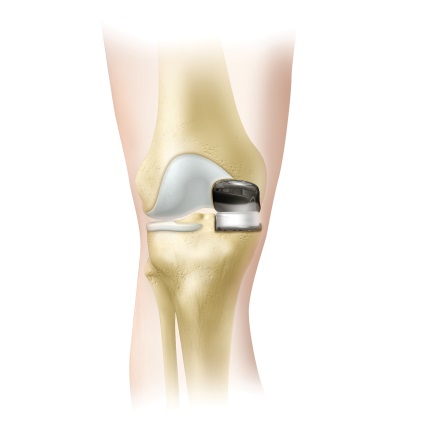

Ahhoz, hogy a megfelelő látható a teljes hiánya a közös tér, a bal oldalon látunk egy sor belső protézis, amely mentesíti a beteget a fájdalom.

Példa behelyezve csípöímplantátum. Az is látható, hogy a bal közös már van egy átlagos mértéke coxarthrosis.